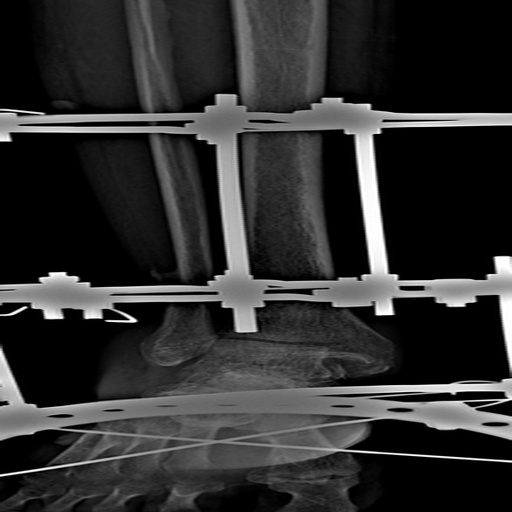

It identifies hairline fractures in medical imaging